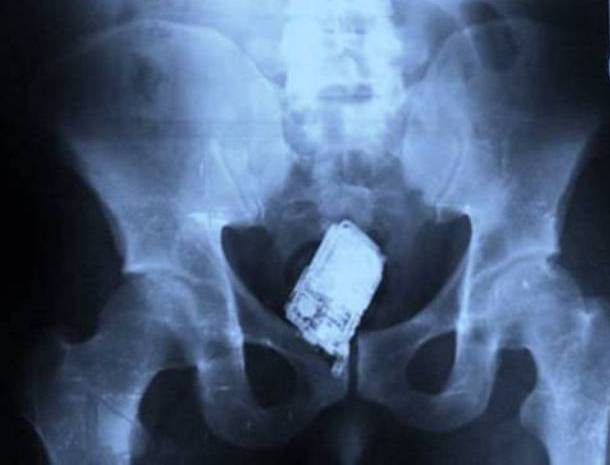

11. ...và một chiếc điện thoại nắp gập nữa...

Mọi tình tiết của sự vụ này y chang như trường hợp bên trên, chỉ khác là nó xảy ra ở San Salvado, và dị vật lần này là một chiếc điện thoại nắp gập hiệu Siemens.